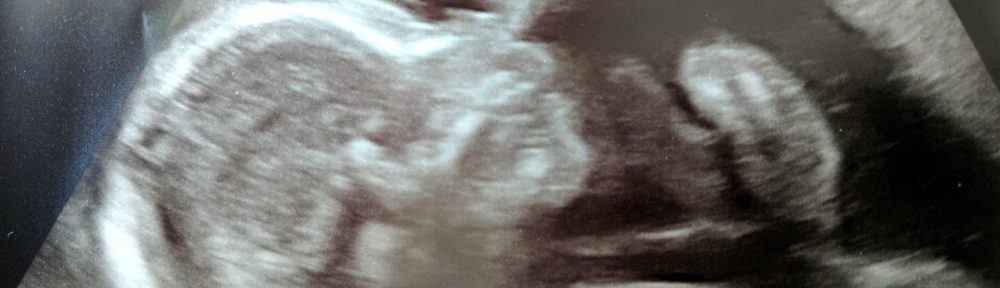

Cheryl and I went to hospital for the 20-week scan today. We were told there was a good chance of finding out the gender of our child. Within a minute if the scan starting we were told we were having … Continue reading Jake, my son